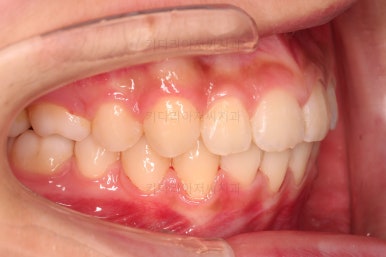

1. 초진 시 입안의 모습 평가

부산치아교정치과 키다리아저씨치과에 처음 내원했을 당시의 입 안의 모습입니다.

전반적으로 윗니가 나와있는 양상이고요.

앞니는 뻐드러져 있네요.

아래 앞니는 위로 솟구쳐 올라서 윗니 뒤쪽을 강하게 치고 있는 과개교합 양상이었고요.

위아래 앞니쪽이 삐뚤어져 있는 상태였습니다.

이번 학생은 입 안의 모습에서 보시다시피, 위아랫니가 앞뒤로 차이가 많이 나는 편이었는데요.

보통은 윗니가 튀어나온 돌출이라고 생각하고 부산치아교정치과 내원을 하시지만 이번 환자분도 아래턱이 작아서 문제가 시작된 경우였습니다.

아래턱이 작다 -> 위아래 앞니가 만나지 않는다 -> 아랫니는 윗니와 만나려고 솟구쳐 오른다(과개교합) -> 앞니가 앞뒤로 멀고 과개교합이면 아랫입술이 안으로 말려 들어간다.